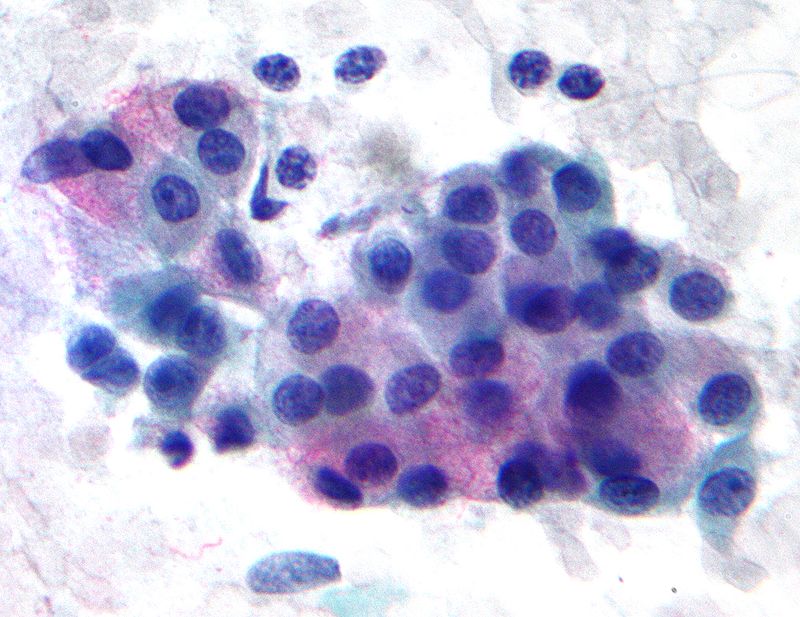

Warthin tumor is a benign cystic tumor with a stroma that resembles a lymph node and many lymphocytes.

Warthin tumor is also known as papillary cystadenoma lymphomatosum.

Warthin tumor is the second most common salivary gland tumor.

Warthin tumor occurs almost invariably in the parotid.